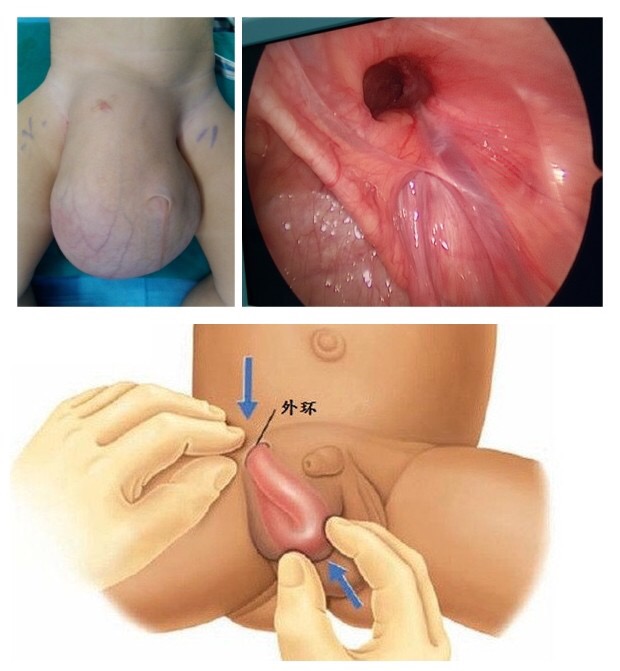

A:陰囊睪丸鞘膜積液通常主要的治療是採用手術治療,但是對於小兒、嬰幼兒的鞘膜積液,有自然消退的可能性,通常可以暫時無須治療。對於成人較小的鞘膜積液,也可以採取保守觀察的方法。對於急性炎症引起的鞘膜積液、外傷性鞘膜積液,可以自行消退,需要控制原發……

A:對於一歲半的鞘膜積液,要明確診斷是哪種類型的鞘膜積液,是否可以自愈需要根據情況判斷,說明如下:1、單純性鞘膜積液:可以先觀察隨訪,不做處理,因為兩歲以下的兒童鞘膜積液多可自行吸收,嬰幼兒的鞘膜積液禁忌抽吸;2、交通性鞘膜積液:則考慮要進……

A:正常情況下睪丸鞘膜腔內是可以有一些液體的,保證睪丸在陰囊內具有一定的活動範圍,隨著睪丸陰囊鞘膜腔的液體增加,我們稱之為鞘膜積液。鞘膜積液可以分成睪丸鞘膜積液、精索鞘膜積液或者混合型的鞘膜積液,以及交通性鞘膜積液和嬰幼兒的鞘膜積液,鞘膜積液在……